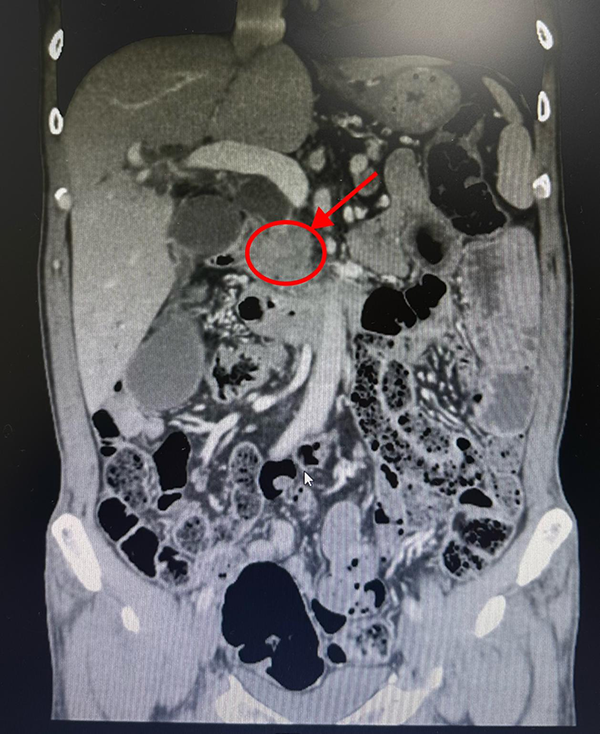

胰头肿物

通过了解患者病情,及一系列相关检查,充分判断肿瘤大小、位置和与周围血管关系,李松主任发现肿瘤严重侵犯血管,并且像这样的情况,常伴有肿瘤周围血管增生,肿瘤切除异常困难,加之需进行血管吻合重建,难度系数非常大,稍有不慎就会出现大出血,甚至危及生命。